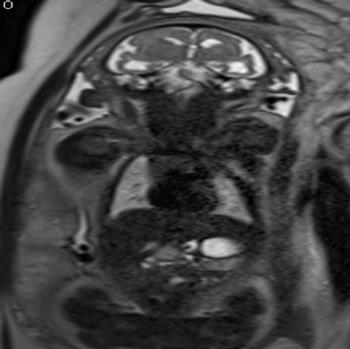

Another study analyzed the imaging results of three target groups affected by Zika: adults who developed acute neurological syndrome, newborns with vertical infection with neurological disorders, and pregnant women with rash outbreaks suggestive of Zika.

Many of the adults had symptoms of Guillain-Barré syndrome, a rare disorder in which the body's immune system attacks the nervous system causing rapid onset muscle weakness. A few showed inflammation of the brain and spinal cord (Bickerstaff's encephalitis) or brain stem and spinal cord lesions. Common MRI findings included enhancement of certain spinal and facial nerves. In the newborns, MRI showed orbital injuries and anatomical changes in brain tissue.

In a third study, ultrasound and fetal MRI were performed on pregnant patients with Zika virus infection at different gestational ages. Once the babies were born, they underwent ultrasound, CT and MRI. The researchers then created 3-D virtual and physical models of the skulls. More than half the babies had microcephaly, brain calcifications and loss of brain tissue volume, along with other structural changes.